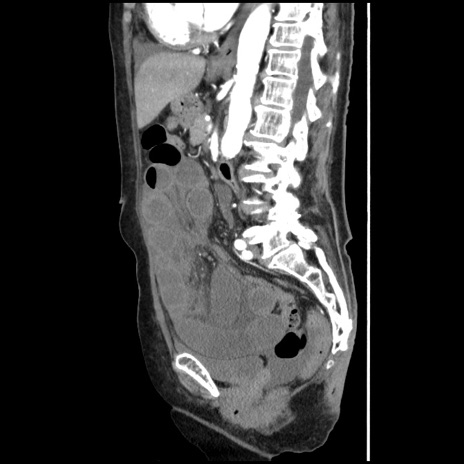

症例1(矢状断像)

【症例】80歳代女性

【主訴】腹痛

【現病歴】8時間前から腹痛あり来院。

【既往歴】糖尿病、脂質異常症、子宮体癌にて子宮全摘術

【身体所見】意識清明・会話良好だが腹痛で苦悶様、全腹部にわたって反跳痛と圧痛あり

【データ】WBC 13600、CRP 0.14、LDH 224、CK 90